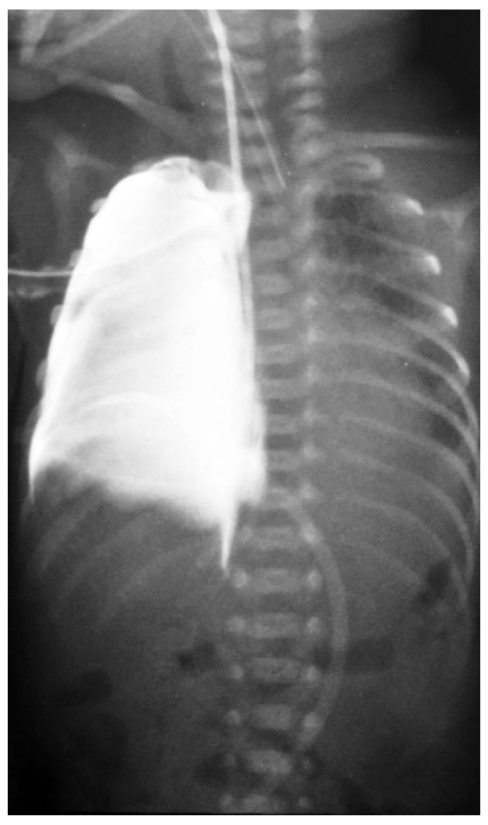

Рентгенологическая картина миграции желудочного зонда из просвета пищевода в окружающее пространство может быть различной и мало зависеть от локализации самой перфорации (рис. 2–4). Затёк контрастного вещества в плевральную или брюшную полость, средостение или забрюшинное пространство мы встречали при перфорации грушевидного синуса, глоточно-пищеводного перехода и нижней трети пищевода.

Рис. 2. Контрастная рентгенография органов грудной и брюшной полости: затёк контрастного вещества (йогексол в объёме 3,0 мл) в забрюшинное пространство

Fig. 2. Thoracic and abdominal contrast study: leakage of contrast medium (Iohexol, 3 cc) into the retroperitoneal space

Рис. 3. Контрастная рентгенография органов грудной и брюшной полости: миграция конца желудочного зонда в правую плевральную полость, гидроторакс

Fig. 3. Thoracic and abdominal contrast study: migration of nasogastric tube tip into the right pleural cavity (hydrothorax)